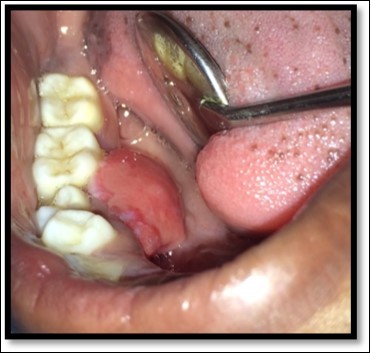

During the next visit local anesthesia was given. The lesion was excised with the help of soft tissue laser and sent for histological examination. (Figure 2) Histological report confirmed the lesion is Peripheral cemento-ossifying Fibroma. Histological analysis showed lesional tissue comprising of both trabecular bone and woven bone. Periphery of the lesion showed numerous globular and irregular cementum like calcification. In most areas these calcification coalesced with each other forming bigger calcification. The supporting connective tissue stroma was loose fibrillar with less cellularity. Detached overlying parakeratinized epithelium was observed in one area. (Figure 3) Post operative evaluation revealed normal healing after one month. (Figure 4)

Figure 3.Histologically H & E stained section shows trabecular bone and woven bone more towards the center of the lesion

Histologically H & E stained section shows trabecular bone and woven bone more towards the center of the lesion